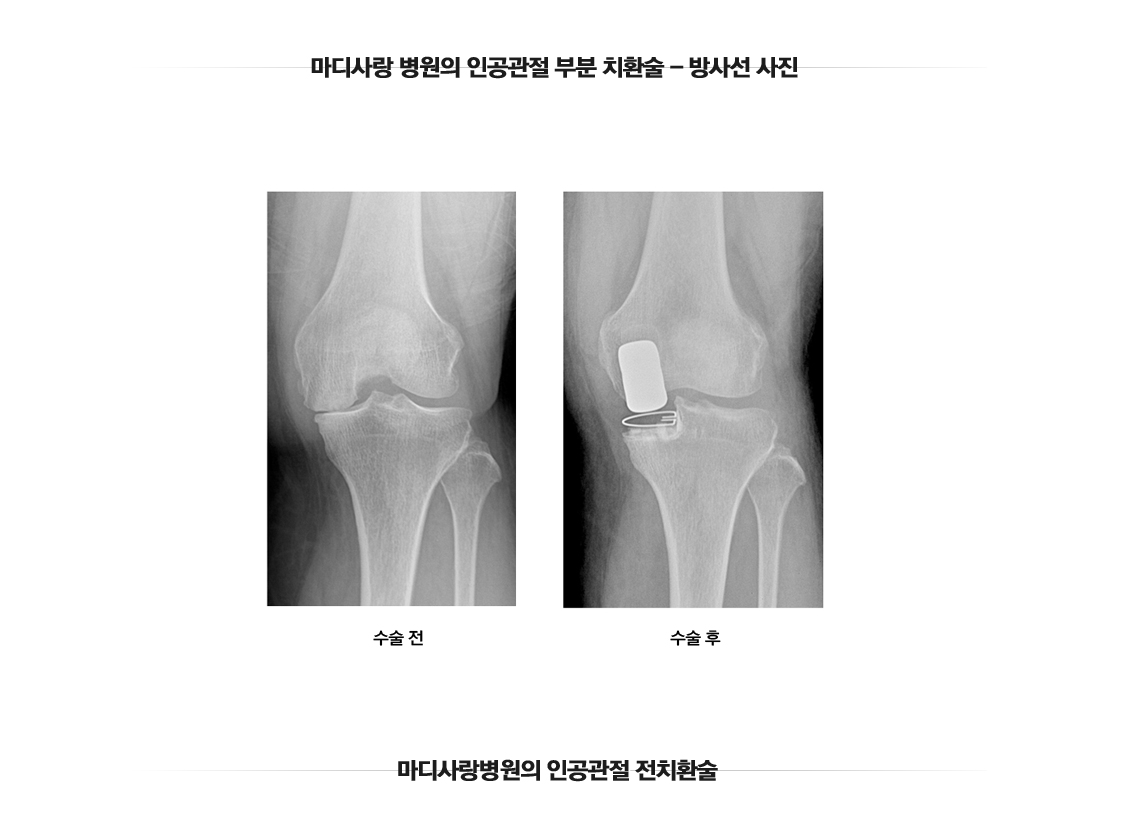

인공관절 부분치환술

무릎 인공관절 반치환술